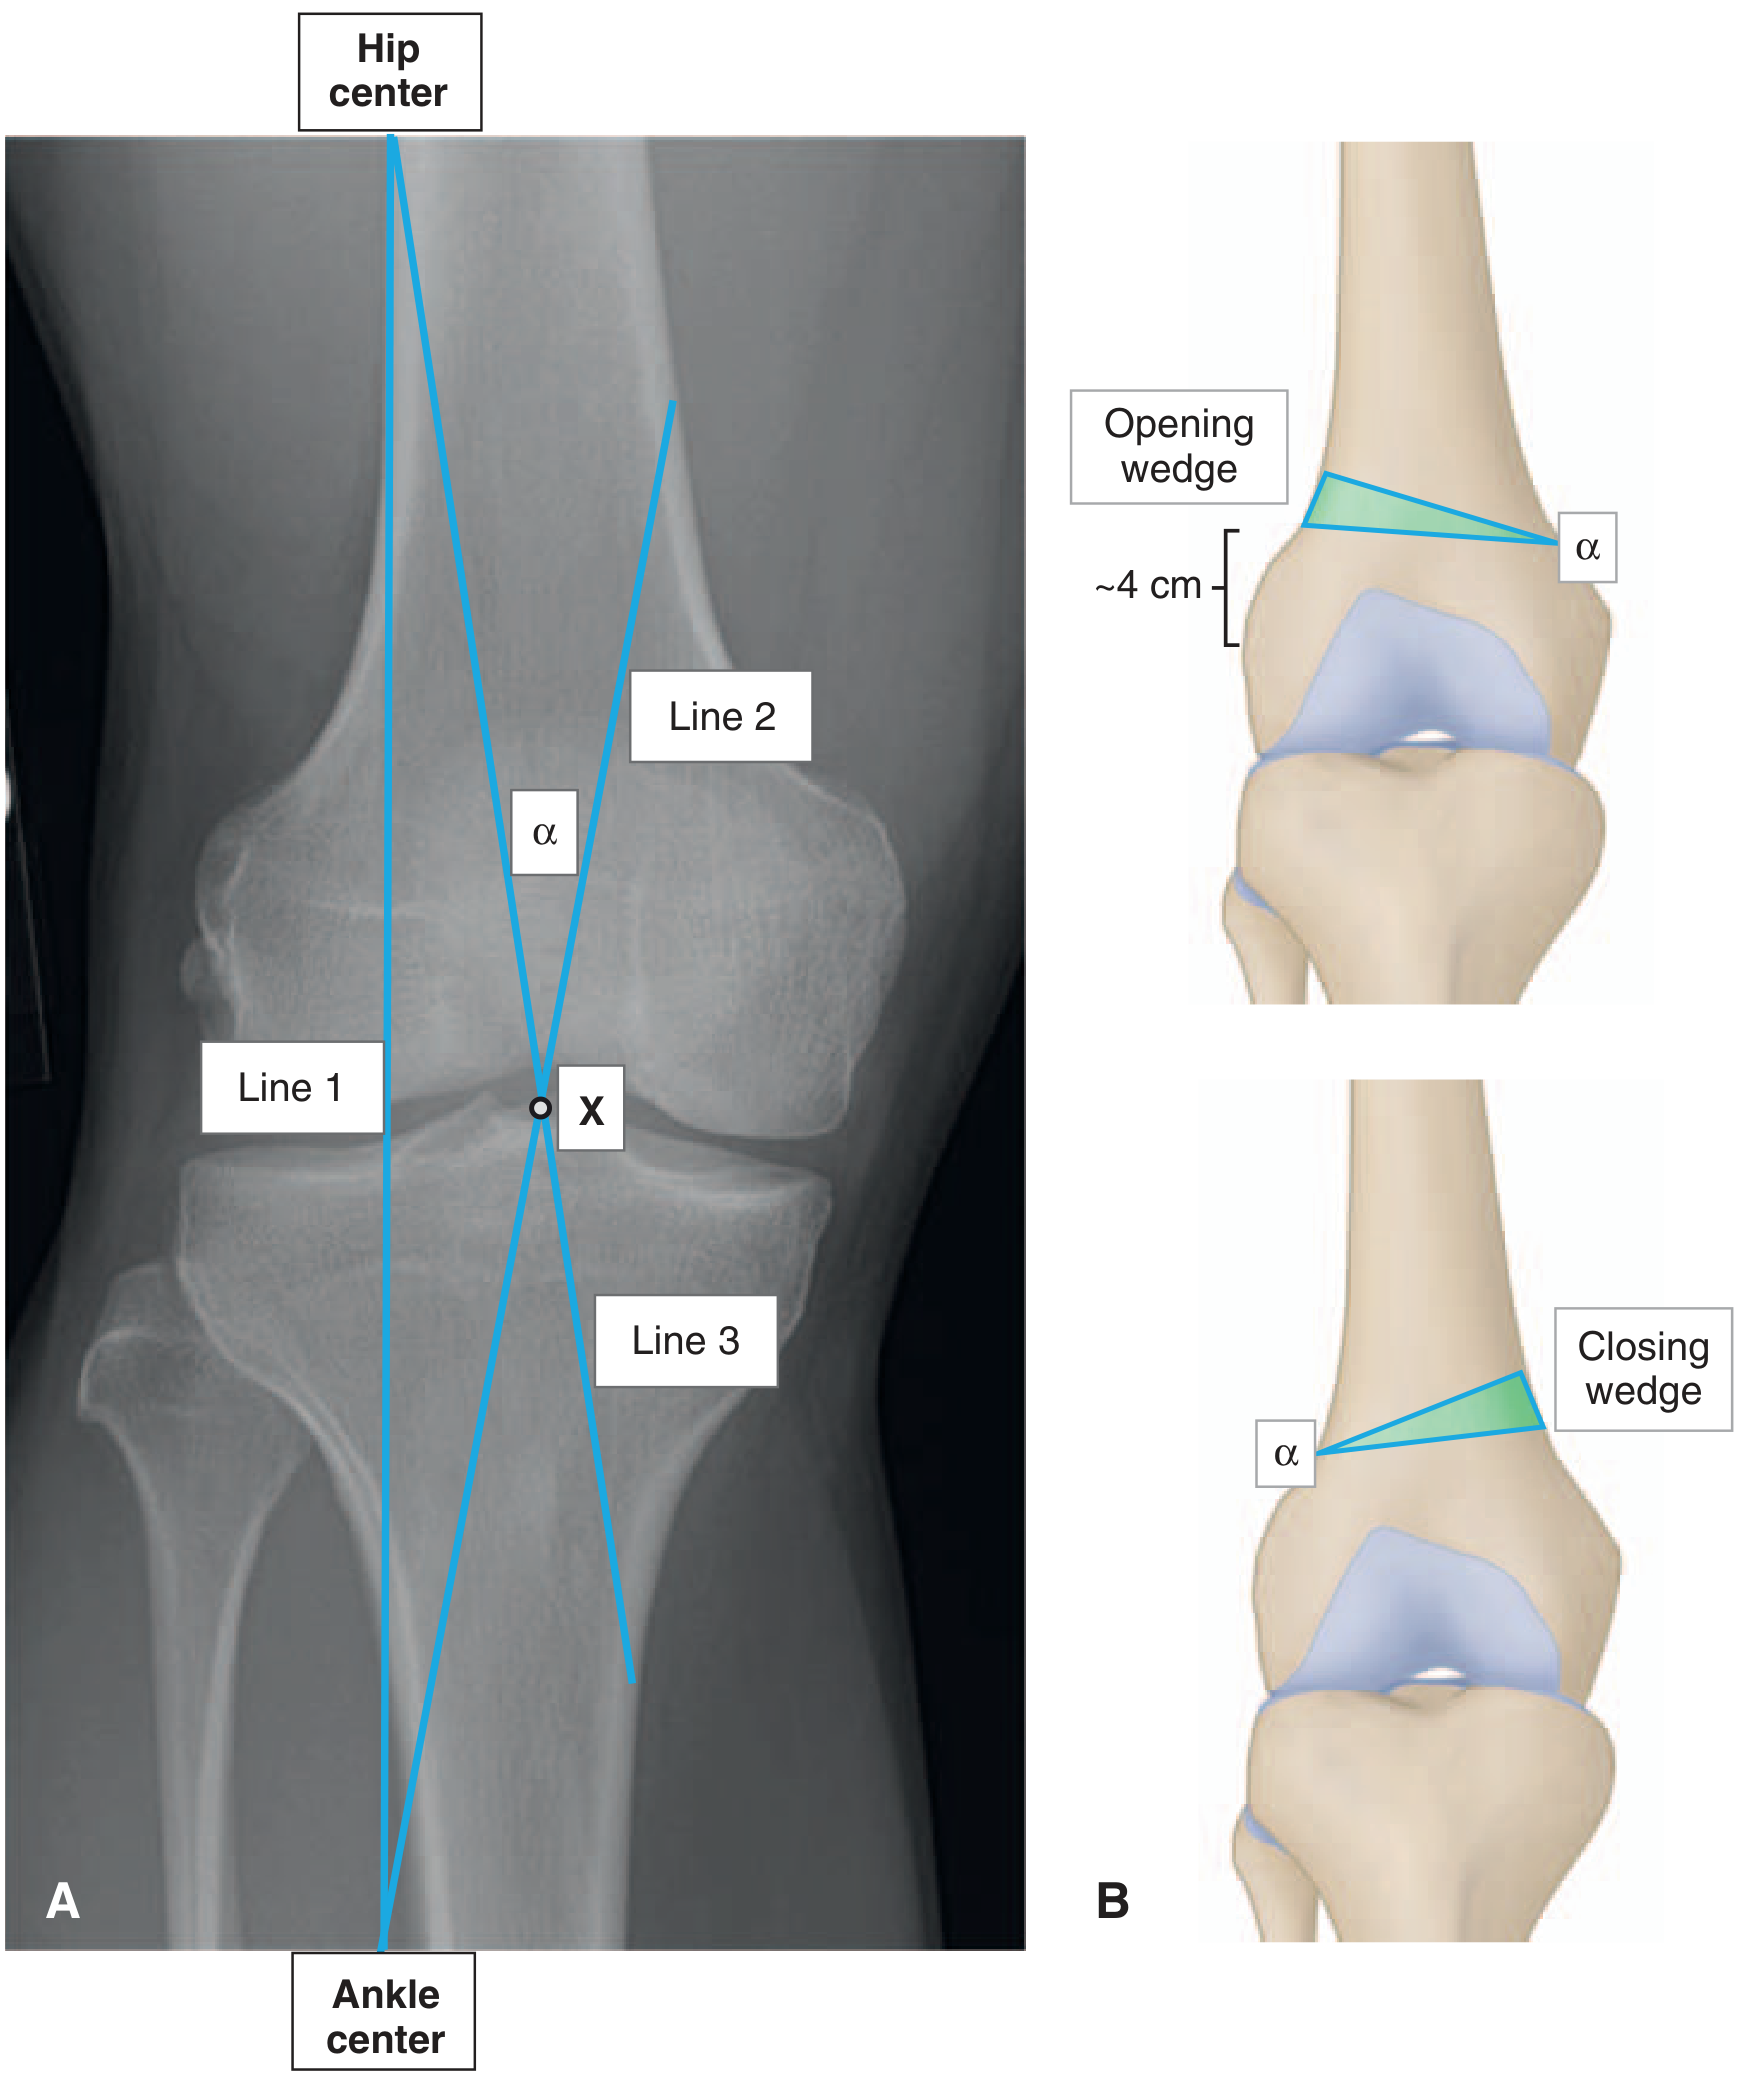

Diagram 4 โ€” Mechanical Axis Measurement & Osteotomy Planning

Long-leg weight-bearing radiograph section showing mechanical axis lines (from hip centre to ankle centre), point of correction X on tibial plateau, and angle ฮฑ for distal femoral varus osteotomy planning:

Distal femoral varus osteotomy planning on AP weight-bearing long-leg radiograph. Line 1 = mechanical axis (hip centre to ankle centre). Point X = correction point on tibial plateau. Angle ฮฑ = correction angle. Opening wedge and closing wedge osteotomy illustrations shown.